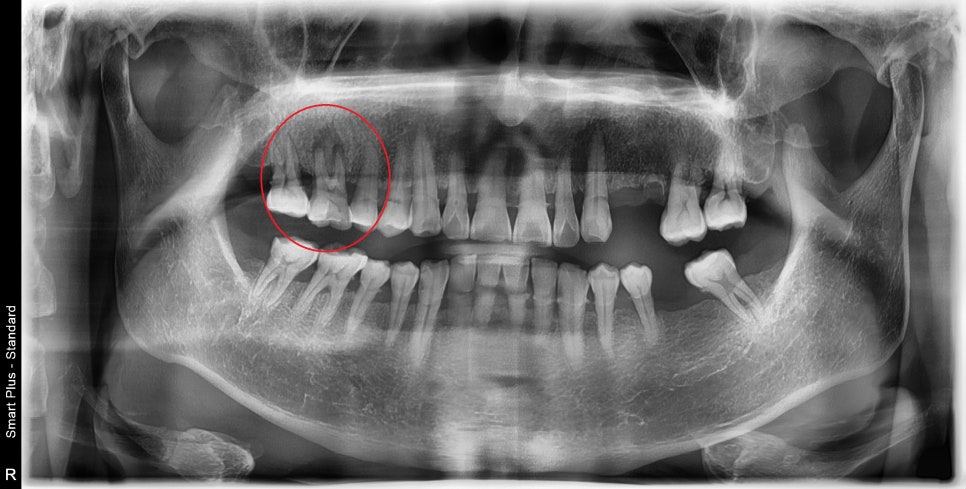

처음 환자분을 검진하기 전 사진을 봤을 때

왼쪽 치아가 다수 상실된 상태에서 우측으로 주로 씹다 보니 가장 일을 많이 하는 치아인

첫 번째 큰 어금니가 망가진 것이 보였습니다.

구내 사진을 찍고 검진을 했을 때 이 치아는 예후가 좋지 않다고 설명을 드렸습니다.

아마도 치아가 깨지며 자극들이 신경관 쪽에 전해져 뿌리 쪽에 염증을 일으키며

지속적인 통증을 유발했을 것입니다.

그리고, 이미 치아의 마모도 및 치아의 깨진 흔적을 봤을 때 굉장히 강한 저작력과 그로 인해

치아에 금이 가있을 확률이 높았습니다.

잇몸뼈 또한 입천장 쪽으로 녹아 있었기 때문에 이 치아는 그동안 너무 많은 일을 해왔고, 수명이 얼마 남지 않았습니다.